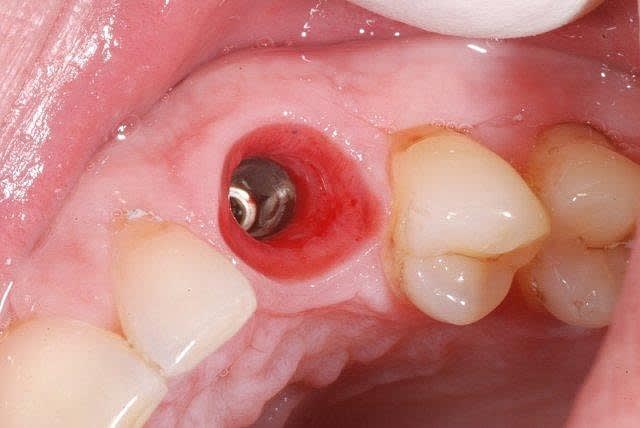

19/08/2011 à 15h42

au fait, suite à ce cas:

réouverture ce matin, le volume obtenu par la greffe est conservé, os densité D2-D3.

Aspect gingivaln k2j20s - Eugenol

L implantn eftzk3 - Eugenol

il est effectivement assez réjouissant, à chaque réouverture, de retrouver un volume identique à celui obtenu le jour de la greffe. De plus, la densité est suffisante pour obtenir une stabilité primaire compatible avec de la reconstitution immédiate ce que je n'ai pas entrepris ici car ce jeune homme est rugbyman (je l'avais d'ailleurs bien mis en garde pour ce qui était de la greffe et des précautions à prendre lors de la pratique de son sport, lui conseillant la philatélie plutôt que son sport favori durant quelques semaines:)

L'implant est un 3.7 x 12 mm, j'aurais pu poser un 4.2 mais j'aime bien garder une bonne épaisseur d'os autour de l'implant et notamment en vestibulaire. La temporisation est assurée par un petit partiel amovible qu'il portait déjà depuis plusieurs années. Le challenge maintenant est, à la mise en fonction, de réaliser une dent provisoire anatomique afin de préparer une belle émergence gingivale (par exemple comme ce cas de canine sur les 2 photos que je vous joins avec ce post) et obtenir ainsi un résultat final le plus naturel possible.

Pour n'avoir rencontré, pour le moment, que des succès avec l'usage de ce type de greffons, je trouve qu'ils constituent pour mon usage personnel une excellente alternative aux prélèvements autologues pour un coût similaire (diminution de la durée d'intervention, qui le sera peut-être d'ailleurs encore plus à l'avenir avec le façonnage 3D pré-opératoire des greffons Biobank initié et essayé par Pxav). Reste maintenant à suivre les cas de près dans le temps pour évaluer la stabilité du volume à long terme.